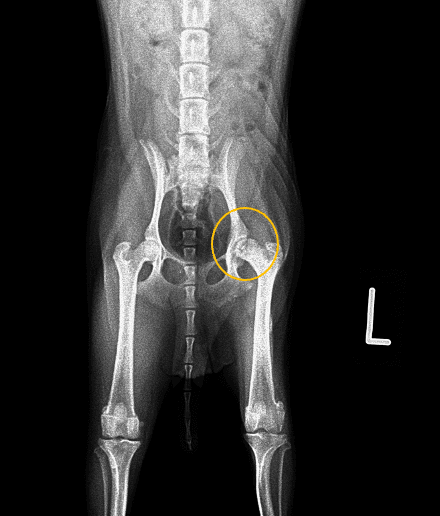

レントゲン検査をおこなったところ、写真のように大腿骨頭と呼ばれる部位が黒く抜けていることが分かりました。このような所見や発生状況から大腿骨頭壊死症(レッグ・カルベ・ペルテス病)と診断しました。

画像の黄色で囲ったところが病変部位です。